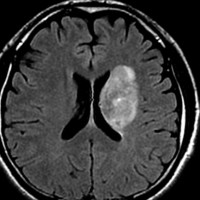

放射線治療後9週目

フレア画像です。たった2週間で脳浮腫が高度の脳浮腫となっています。失語症と右片麻痺と認知機能低下が生じました。ステロイド剤とグリセリンの点滴を行いました。